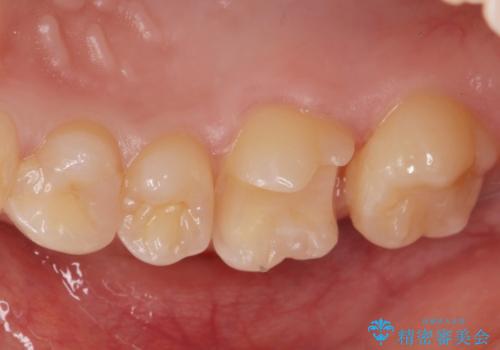

コンタクトカリエスの治療。(e-maxインレー)

- 歯が染みるとの事で来院。歯と歯の間にカリエス(虫歯)が出来ていて穴が空いていました。

拡大鏡下で虫歯を全て取り除き、e-maxインレーで治療を行いました。

適合の良い詰め物が入りました。

歯と歯の間の虫歯は歯ブラシでは予防しずらく、フロスを毎日行わないと虫歯になります。